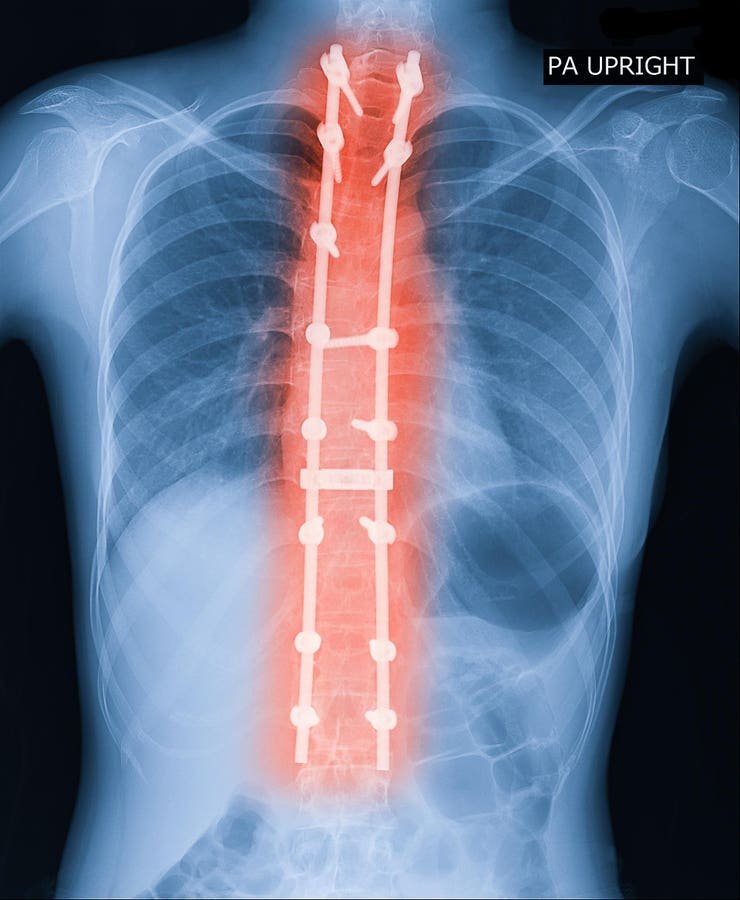

X -ray image of the adult spine showing scoliosis surgery. Scoliosis surgeries are effective but accurate.

Adult symptomatic lumbar scoliosis (ASLS) is a complex challenge in spine care, deeply affecting the quality of life through pain, disability and spine deformation. This condition, characterized by lateral curvature in the lumbar spine of adults, differs from pediatric scoliosis. While pediatric scoliosis usually occurs during development, ASL often results from degenerative changes in the lower back. Pain is a main symptom in most cases of adults, as opposed to the majority of pediatric cases. In addition, because adult spines are less flexible, surgeries often require more invasive techniques, such as osteotomies or bone cuts, to achieve spine alignment.